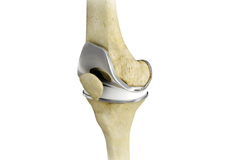

Total Knee Replacement

A Total Knee Replacement (TKR) or Total Knee Arthroplasty is a surgery that replaces an arthritic knee joint with artificial metal or plastic replacement parts called the 'prostheses'.